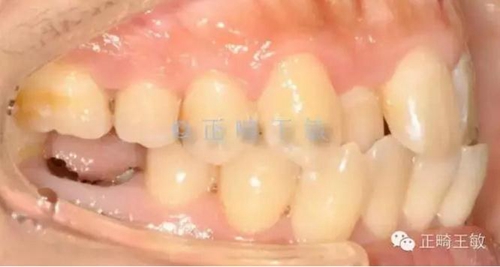

只是偏合,為了糾正,47的支抗不免喪失,最終會(huì)做成一個(gè)這樣的關(guān)系。

7.jpg

這時(shí),順理成章的種一個(gè)小一點(diǎn)的46,同樣是尖窩相對(duì),同樣的穩(wěn)定。

8.jpg